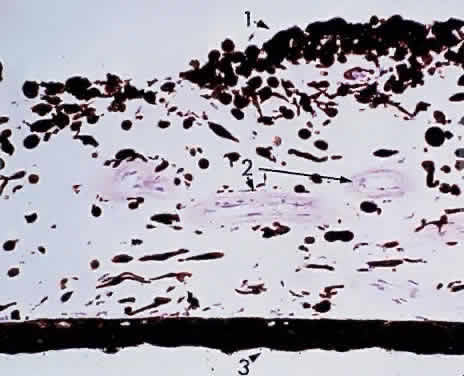

The choroid may be classified in layers, from the external to the internal surface. The suprachoroid is the space between the inner pigmented sclera (lamina fusca) and the large vessels of the choroid. The large-vessel layer (Haller's layer) is the outermost layer of the choroid. It is characterized by wide-caliber veins and arteries. Many melanocytes and ciliary nerve fibers are scattered throughout the vessel layers. The melanocytes and the Schwann cells encasing the nerve fibers, along with an occasional cluster of nevus cells, may be the precursors of the dreaded malignant melanoma of the choroid. The medium-vessel layer (Sattler's layer) is composed of medium-sized blood vessels and is located in the center of the choroid. The choriocapillaris is a layer of very large fenestrated capillaries (40 to 60 μm in diameter) lying in a single plane external to Bruch's membrane (Fig. 18; no fenestration of the choriocapillaris is visible at this level of magnification). The capillary lumina are large enough to pass several red blood cells simultaneously (Fig. 19). Unlike the larger vessels in the choroid, the fenestrated choriocapillaris lacks an internal elastic lamina and therefore leaks fluorescein during clinical angiography. Pericytes are found on the outer wall of the capillaries. Postmortem injection studies suggest that the choriocapillaris is continuous, but the choriocapillaris functions clinically like an end arteriole network. At the posterior pole, the choriocapillaris has a lobular pattern with a central precapillary arteriole and a peripheral postcapillary venule.

Fig. 18. Choriocapillaris at macula under Bruch's membrane and the retinal pigment epithelium (retina is detached) (× 800, KEI 71125).

Fig. 19. Choriocapillaris at macula shows red blood cells in rouleaux pattern (retina is detached) (× 800, KEI 71125).

Scanning electron microscopy reveals three patterns of vascular structures in the choriocapillaris. At the posterior pole, the capillaries assume a lobular pattern. This architecture of the macular areas choriocapillaris makes it ideal for photodynamic therapy for “wet” macular retinal degeneration. At the equator, the pattern is spindle-shaped, and at the periphery, the capillaries have a ladder pattern. This structure explains the various degrees of flushing of fluorescein during angiography.

In the foveal zone, the sole vascular supply to the retina is the choriocapillaris. In central retinal artery occlusion, a major portion of the retinal circulation is blocked, and ischemia results. The cherry-red spot represents the intact choriocapillaris providing continued nutrition to the overlying area of macular photoreceptors. If a cilioretinal artery is present, this tiny vessel may be adequate to save the eye from blindness after a central retinal artery occlusion. The choriocapillaris circulation also acts as a heat diffuser to protect the macula from the heat generated by light rays striking the retina. This protection may be diminished by aging or disease, resulting in a reduction of central vision by heat phototoxicity, and may be a factor in age-related maculopathy.